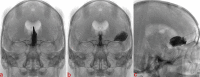

Background and Objectives Few simulation models are available that provide neurosurgical trainees with the challenge of distorted skull base anatomy despite increasing importance in the acquisition of safe microsurgical and endoscopic techniques. We have previously reported a unique training model for skull base neurosurgery where a polymer is injected into a cadaveric head where it solidifies to mimic a skull base tumor for resection. This model, however, required injection of the polymer under direct surgical vision via a complicated alternative approach to that being studied, prohibiting its uptake in many neurosurgical laboratories. Conclusion We report our updated skull base tumor model that is contrast-enhanced and may be easily and reliably injected under fluoroscopic guidance. We have identified a map of burr holes and injection corridors available to place tumor at various intracranial sites. Additionally, the updated tumor model allows for the creation of mass effect, and we detail the variation of polymer preparation to mimic different tumor properties. These advancements will increase the practicality of the tumor model and ideally influence neurosurgical standards of training.